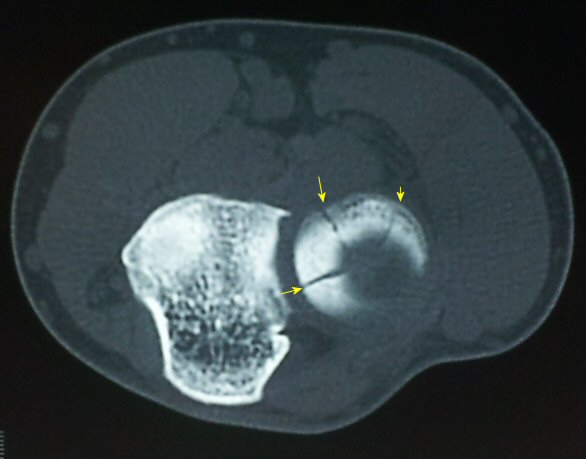

ÀÚ±â°ø¸í°Ë»ç

°ËÇ»ÅÍ ÃÔ¿µ : ¿ä°ñ µÎ ÀåÃà¸é °ñÀý( ±×¸² 6. 7)